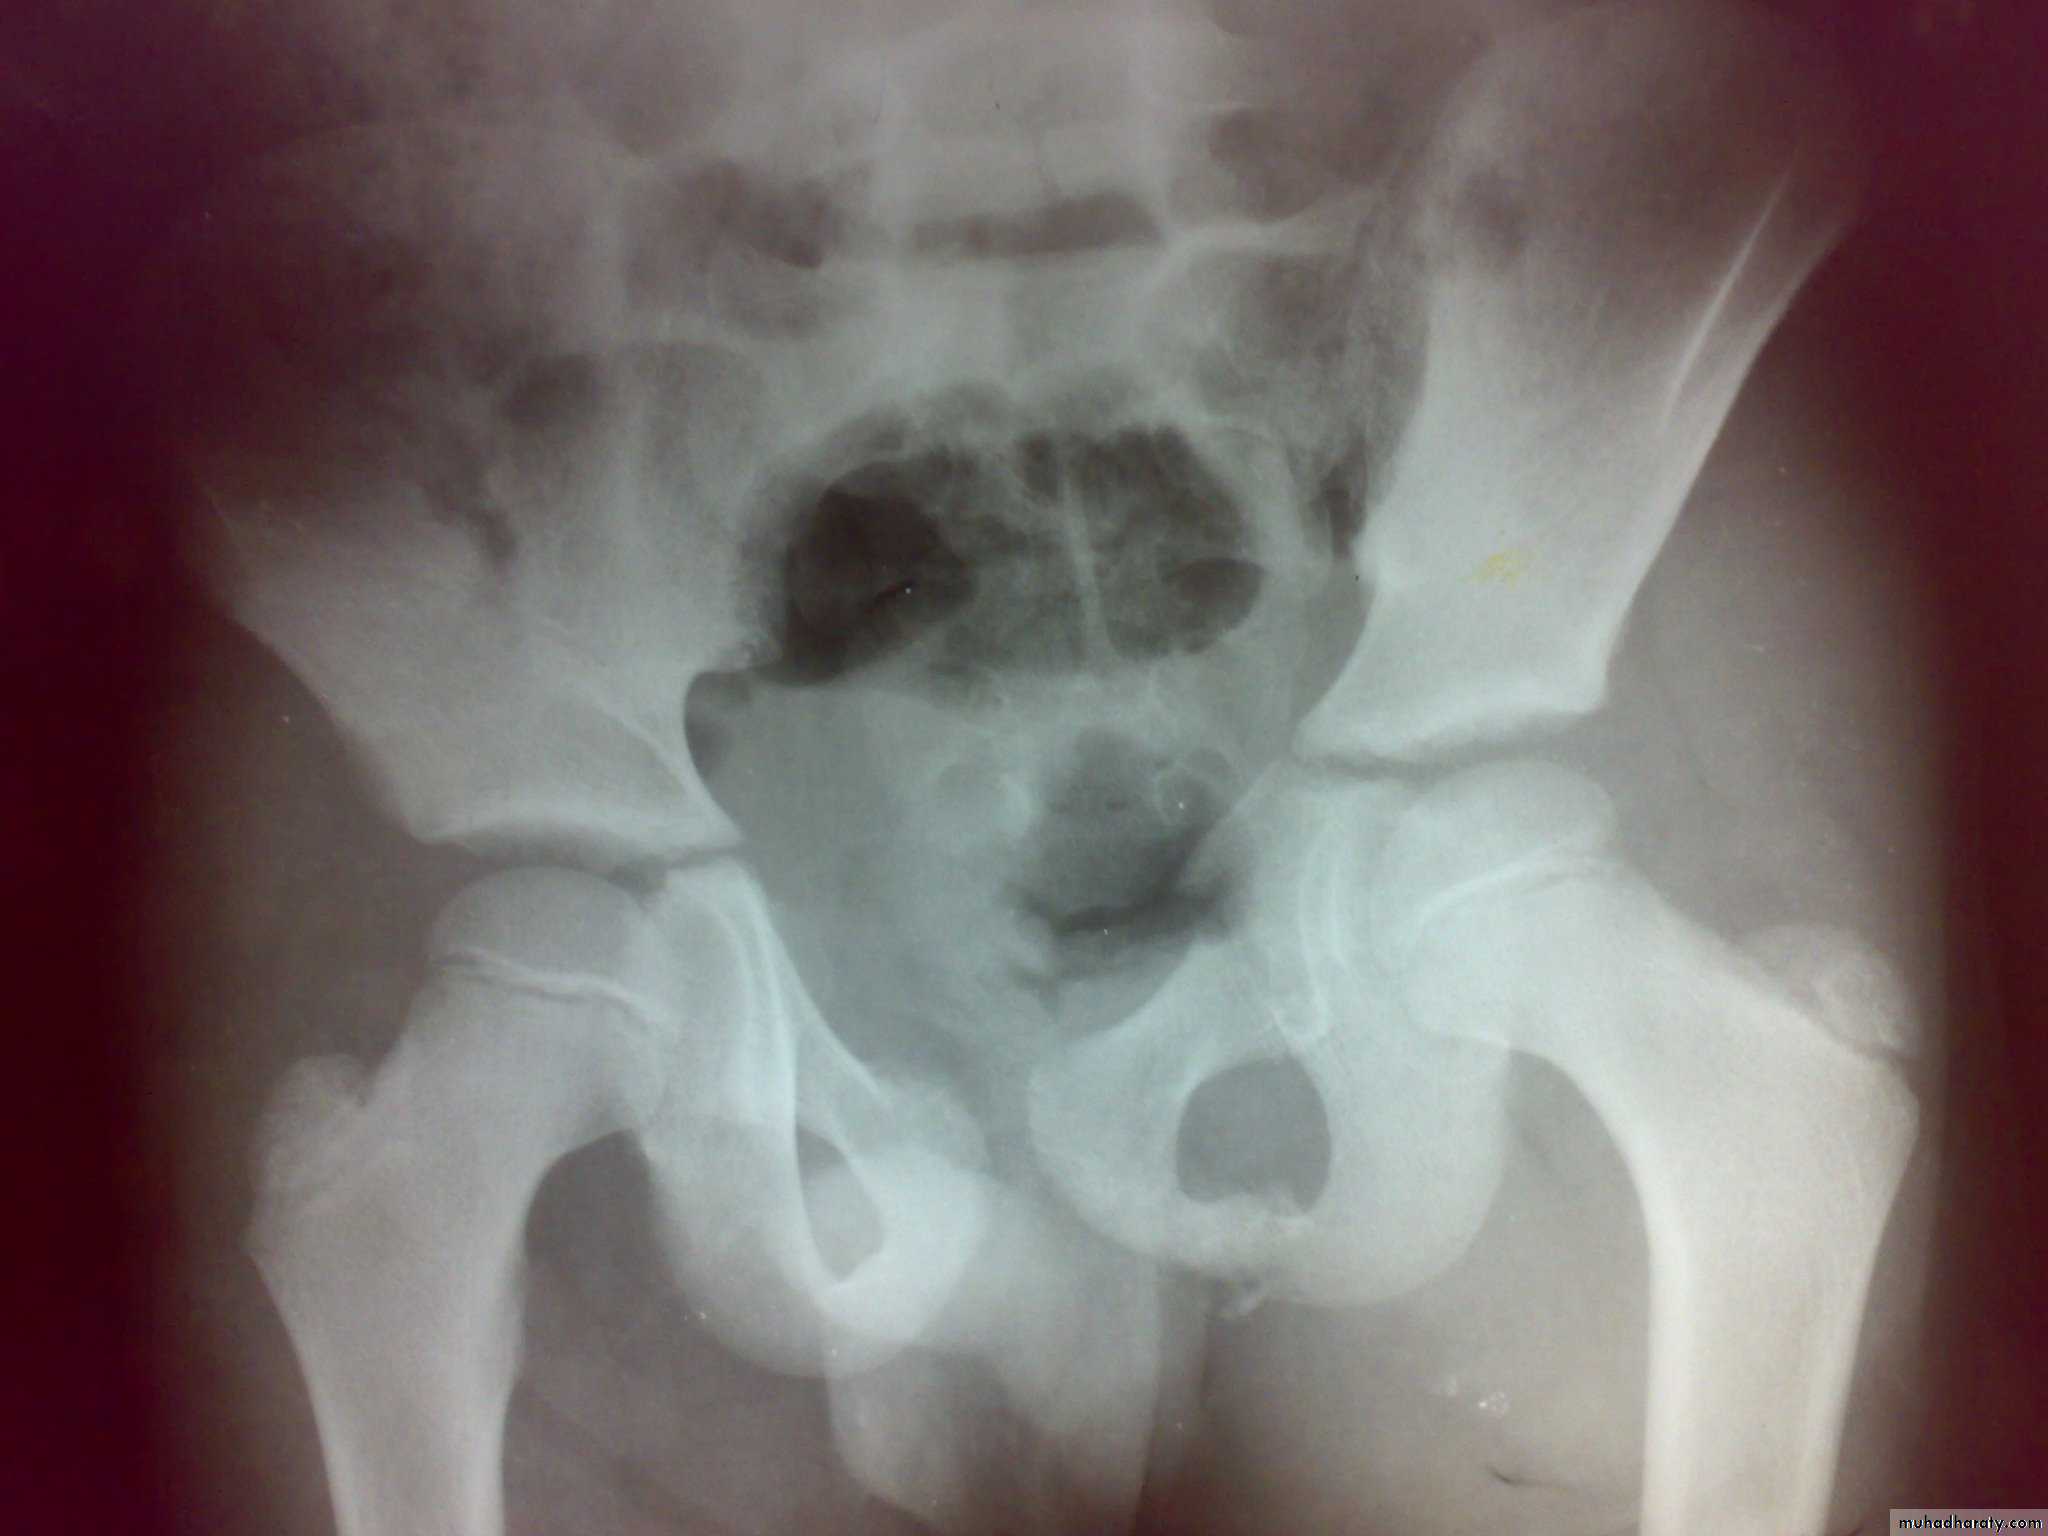

Fracture pubic ramai

Fracture pubic ramiFracture acetabulum